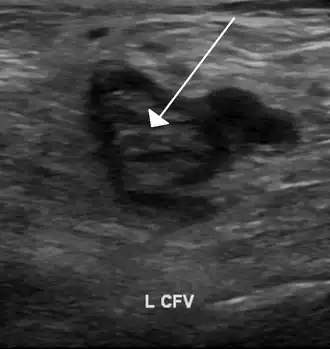

| Тромб в левой бедренной вене на УЗИ | |